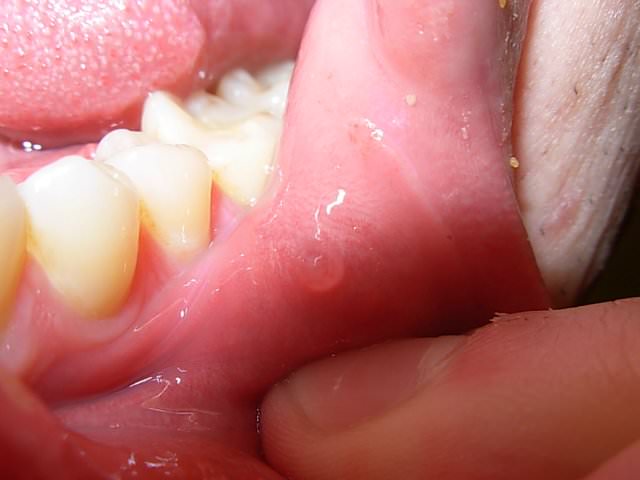

Четкие ровные круглые пятна с отеком и приподнятой коже, под которой явно видна прозрачная или белая с желтоватым оттенком жидкость могут говорить о заражении инфекционным заболеванием или рецидиве хронической болезни.

С неровными отеками, внутри которых также есть содержимое, жидкое или очень плотное, дело обстоит сложнее, такой волдырь может говорить как об ожоге, так и о болезни.

• Волдыри. Они относятся к поверхностным образованиям, содержащим внутри жидкость. Частая причина их появления – ожог.

• Волдырь – поверхностное образование, при рассматривании которого виднеется накопление жидкости под верхним слоем кожных покровов. В случае ротовой полости под неороговевающим эпителием. Такая патология возникает после ожога горячей пищей или воздухом.

С особой осторожностью следует подходить к лечению мелких пузырьков на внутренней стороне щеки.

Пузырьки могут быть наполнены кровью изнутри.

Нельзя прокалывать кровяной волдырь в полости рта и травмировать.

Повреждение волдырей на слизистой может вызвать инфекции, сопровождаемые повышенной температурой и аллергическими реакциями.

Кроме того такие образования можно легко повредить зубами.

Необходимо осторожно поместить между челюстью и пораженной щекой обеззараживающий компресс и обратиться к специалисту.